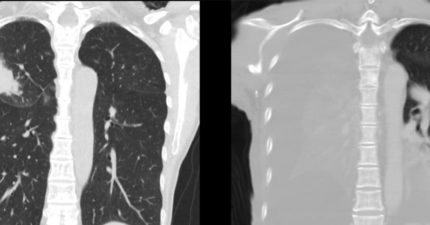

阿嬤餵孫吃整顆花生 1歲孫「肺部開始塌陷」醫氣炸:到底還要講幾次?嬰幼兒的身體尚未發育完全,所以飲食方面要格外注意。小兒科醫師廖穗綾就在臉書粉專分... February 13, 2026 健康, 台灣, 知識